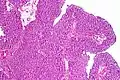

| Histopathology of transitional carcinoma of the urinary bladder. Transurethral biopsy. Hematoxylin and eosin stain. | |

Transitional cell carcinoma, being low-grade to the left, and high-grade to the right. H&E stain

Papillary transitional cell carcinoma, low grade

Histopathology of urothelial carcinoma of the urinary bladder, showing a nested pattern of invasion. Transurethral biopsy. H&E stain

Histopathology of urothelial carcinoma of the urinary bladder.

Micrograph of urethral urothelial cell carcinoma. H&E stain